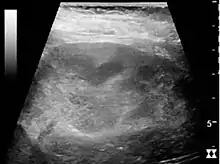

US is useful for diagnostic and prognostic purposes in chronic kidney disease. Whether the underlying pathologic change is glomerular sclerosis, tubular atrophy, interstitial fibrosis or inflammation, the result is often increased echogenicity of the cortex. The echogenicity of the kidney should be related to the echogenicity of either the liver or the spleen (Figure 22 and Figure 23). Moreover, decreased renal size and cortical thinning are also often seen and especially when disease progresses (Figure 24 and Figure 25). However, kidney size correlates to height, and short persons tend to have small kidneys; thus, kidney size as the only parameter is not reliable.[1]

Figure 24. Chronic pyelonephritis with reduced kidney size and focal cortical thinning. Measurement of kidney length on the US image is illustrated by ‘+’ and a dashed line.[1] Figure 25. End-stage chronic kidney disease with increased echogenicity, homogenous architecture without visible differentiation between parenchyma and renal sinus and reduced kidney size. Measurement of kidney length on the US image is illustrated by ‘+’ and a dashed line.[1]

Figure 25. End-stage chronic kidney disease with increased echogenicity, homogenous architecture without visible differentiation between parenchyma and renal sinus and reduced kidney size. Measurement of kidney length on the US image is illustrated by ‘+’ and a dashed line.[1]